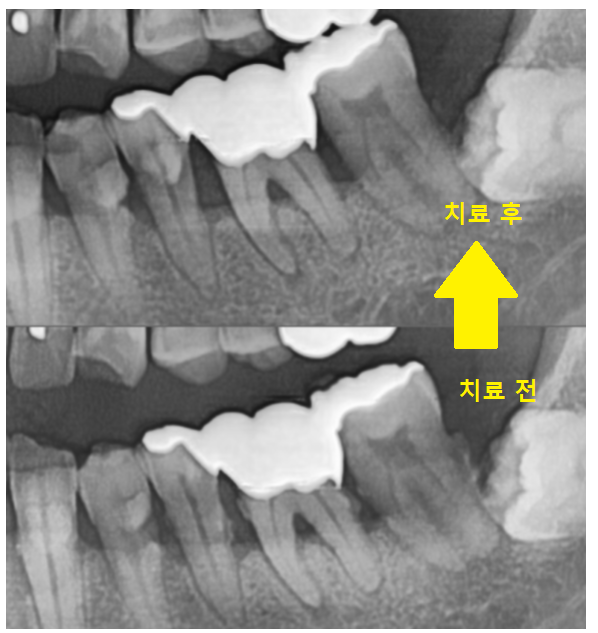

x-ray를 촬영해보니까

치석들이 x-ray 에 보일 정도로 많은 상황이었습니다.

잇몸 밖에 붙어있는 치석 외에도

뿌리쪽에도 있다는 얘기로

치석이 무지 많다는 말입니다ㅎㅎ

23.05.11

잇몸치료 전 잇몸입니다.

치아 뿌리 부분에 울퉁불퉁한 조각들이

붙어있죠~?

상일동역 스케일링을 1차 받고

찍은 사진임에도 큰 치석들이 남아있습니다.

일반적인 치석제거로는

뿌리쪽이 제거가 어렵기 때문에

잇몸치료가 꼭 필요한데요!!

기구를 사용하여 제거

중간중간 제거가 잘 되었는지

x-ray를 찍어 확인해보았습니다.

제거가 다 된듯 하여도

이렇게 사진을 찍어보면

일부 붙어있는 치석들을 볼 수가 있습니다.

남아있는 녀석들을

빡빡 긁어줍니다.

조금이라도 남아있으면

잇몸 염증이 재발하거나

안좋아지기 쉽기 때문에

깨끗하게 긁어 주어야해요~

치료 후 사진을 보시면

깨끗해 진게 보이시죠~?

23.11.18

잇몸 뿌리에 붙어있던 오돌토톨한게

다 사라졌습니다.